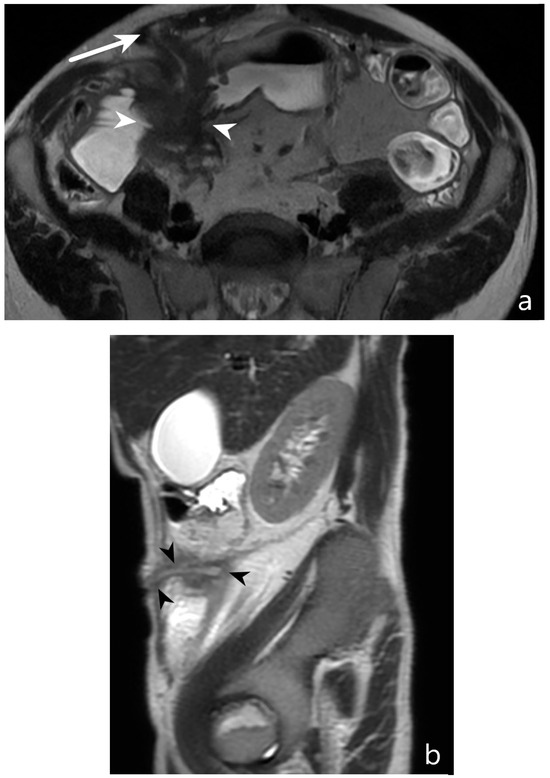

5.3. Fistulising/Perforating Subtype